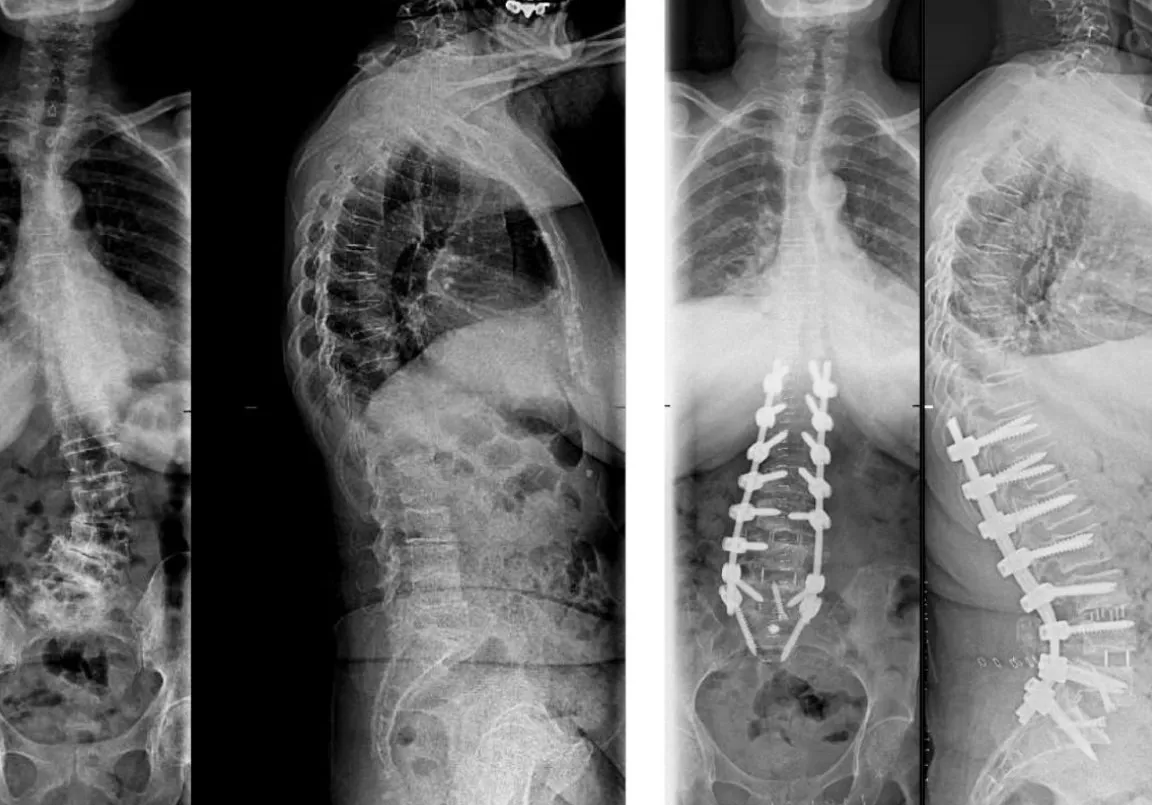

¿Necesito una radiografía o una resonancia magnética?

No es estrictamente necesario para empezar.

Nuestra evaluación física y funcional suele ser suficiente para establecer un diagnóstico y un plan de tratamiento.

Si durante la evaluación detectamos alguna señal de alarma que sugiera un problema más grave, te recomendaremos consultar a tu médico para realizar pruebas de imagen.